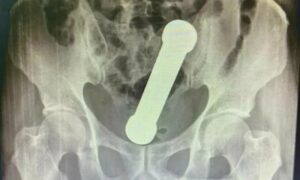

Ao realizarem um raio-x, os médicos ficaram surpresos com o que encontraram no rapaz, pois se tratava de um peso de academia de 20 centímetros, que se usa para exercitar os braços.

O peso estava entre o intestino grosso e reto do homem, que após o vexame, assumiu ter usado o peso para obter prazer sexual.